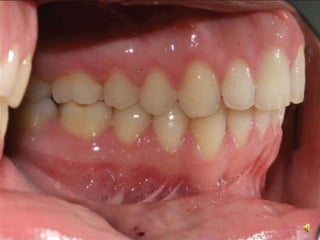

Centric occlusion

Maximum intercuspation between

uppr and lower teeth

Maximum intercuspation

Angle Classification

• Class 1: Mesiobuccal cusp pf maxillary 1st molar occlude in

the buccal groove of mandibular 1st molar

Centric occlusion Maximum intercuspationbetween uppr and lower teeth Maximum intercuspation Maximum interdigitation of the maxillary teeth with mandibular teeth